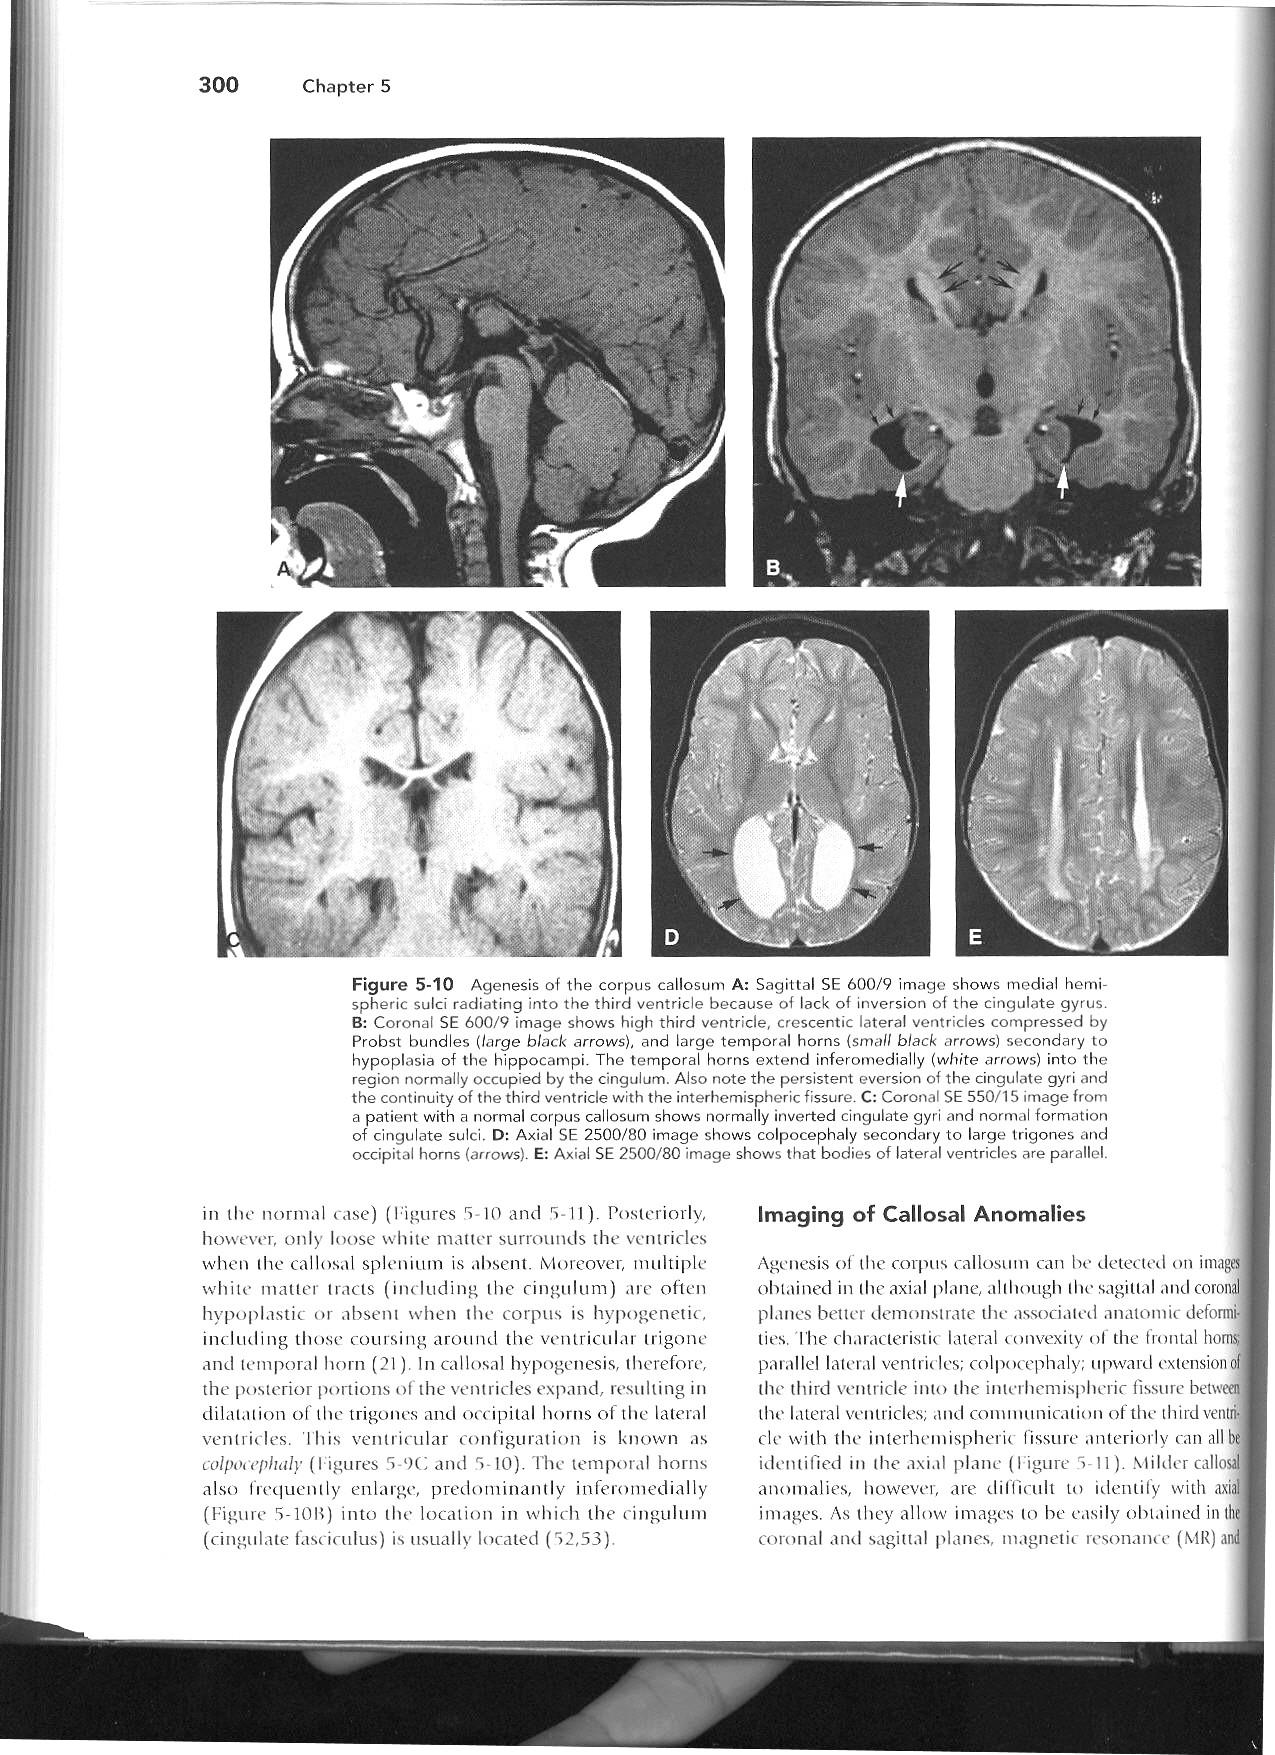

Remember to start with Sweep the Midline… Where is the anterior commissure?

Always finish the sweep looking for second anomaly…

Parallel ventricles

Radial or pallisading gyri in sagittal plane

Colpocephaly

Longhorn or Viking helmit frontal horns

High riding 3rd vent

“Keyhole” temporal horns

Vascular anomalies: “wandering ACAs”

All 3 commissures are absent.

Cingulate gyrus (black arrows) “mirrors” the development of the corpus callosum.

Enlarged HC connects fornices, not cerebral hemispheres